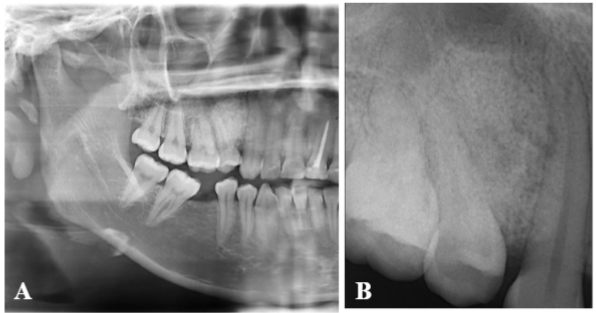

La radiografía panorámica y periapical mostraban un imagen radiopaca de aspecto granular, con forma de pera invertida, localizada entre la pieza 13 y 15, que se extendía desde la cresta alveolar hasta el piso del seno maxilar, en este nivel, bordeando parcialmente la lesión se notaba una línea radiolúcida no bien definida, no había evidencia de reabsorción radicular (figura 2 (a y b). Con los hallazgos clínicos y radiográficos convencionales se plantearon los siguientes diagnósticos diferenciales: osteoma central, osteoblastoma, cementoblastoma, displasia fibrosa y odontoma complejo.